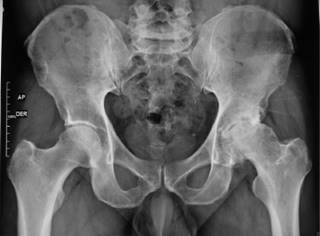

Previa aprobación por los Comités de Investigación y de Ética en Investigación de este hospital (Centro Médico ABC), se efectuó un estudio retrospectivo de todos aquellos casos consecutivos de artroplastía total de cadera, entre Abril de 2018 y Abril de 2020, realizados por abordaje anterior por el mismo cirujano, en el misma institución hospitalaria, igualmente utilizando sistema de reemplazo de cadera con vástago femoral AMIS-H y copa acetabular Versafit-CC (Medacta, Castel San Pietro, Suiza) con liner de polietileno de altos enlaces cruzados y cabeza de cerámica o metal. Se incluyeron 50 caderas en 47 pacientes. Para la totalidad de ellos se formalizó una planificación preoperatoria aprovechando radiografías en proyección anteroposterior con apoyo a una distancia estricta de un metro (Figura 1), proyección anteroposterior de la cadera afectada y proyección oblicua axial a idéntica distancia, así como eje mecánico en la generalidad de los hechos, a excepción de aquellos con fractura de la articulación, a quienes no se les realizó proyección oblicua (Figura 2). Se hizo la medición y selección del tamaño de implantes a utilizar con los sistemas de plantillas específicos de la marca referida. Todos estos afectados tuvieron un seguimiento clínico y radiográfico por 90 días postoperatorios.